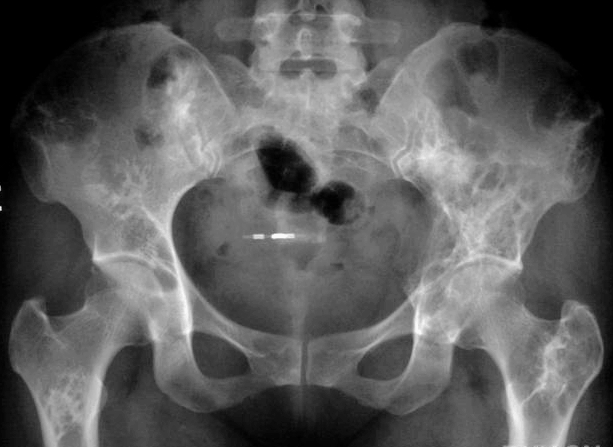

骨盆骨血管瘤病

女,43岁。一个月前无明显诱因出现右侧股部疼痛,呈间歇性钝痛。活动后加重,休息缓解。

结果骨血管瘤病

【abecedarian】网格状改变,符合血管瘤表现,但这么多少见。

临床上发病约在骨肿瘤中约1%,多无性别差异,可发生在任何年龄,但以中年发病较多。表现为局部肿胀、疼痛或为偶有病理骨折。无症状之血管瘤患者,常在尸解时对方被发现。常侵犯脊柱,扁骨次之,肋骨、肩胛骨、髂骨、长骨等其它骨亦可被侵犯。

1.栅栏状或网眼状骨纹 2.囊状骨破坏 3.多囊状骨破坏(多见于海绵状血管瘤) 4.弥漫性骨破坏 5.骨增生性改变

鉴别诊断: 应与巨细胞溜、内生软骨瘤、骨囊肿、动脉瘤样骨囊肿、非骨化性纤维瘤、单骨型骨纤维异常增殖症相鉴别。值得提出,长骨血管瘤与单骨型骨纤维异常增殖症较难区别。但后者病变为较广泛的膨胀性单囊状透亮区,边缘硬化清晰;骨皮质菲薄,囊内有不规则条索状骨纹及斑点状致密影,或呈较均匀无骨纹结构的磨破璃样改变。亦有的呈骨干粗大,骨皮质变薄甚至消失,骨小梁呈粗大扭曲的丝瓜颠状表现。骨外形易变弯曲。这些变化与骨血管瘤的局限性囊状破坏区周围及较远处有不均匀的骨质增生硬化是有区别的。 给大家讲个故事。